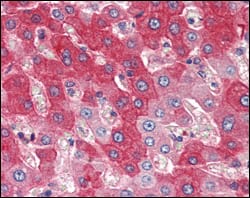

Immunohistochemical analysis of paraffin-embedded human lung adenocarcinoma (A), esophageal squamous cell carcinoma (B), hepatic cell carcinoma (C), thyroid tumor (D), breast adenofibroma (E), breast infiltrating ductal carcinoma (F), normal cerebrum tissue (G), normal colon tissue (H), normal esophageal tissue (I), showing nuclear localization using P16 mouse mAb with DAB staining.

Immunohistochemical analysis of paraffin-embedded human spleen tissues using P16 mouse mAb.